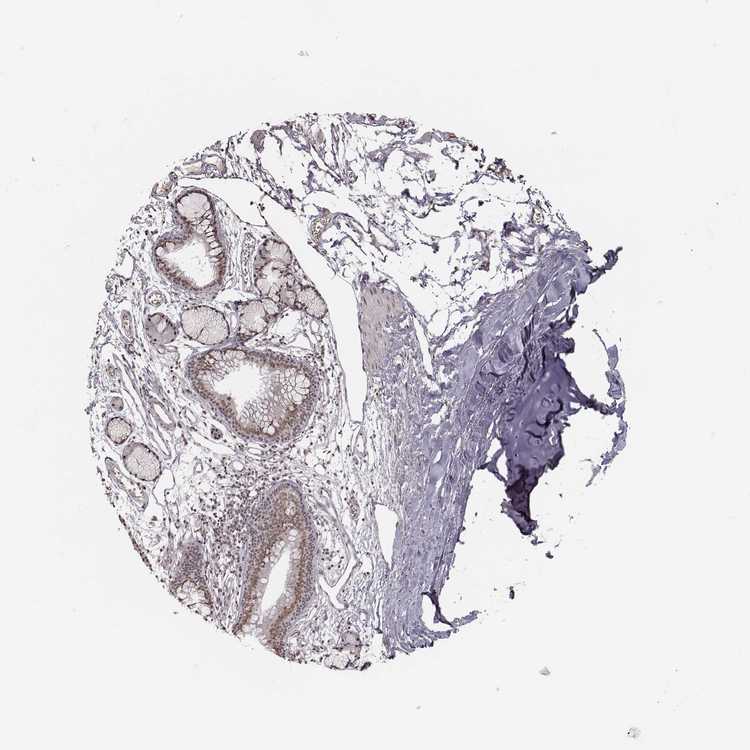

SOFT TISSUE 1 - Antibody stainingi

Antibody staining in the annotated cell types in the current human tissue is reported as not detected, low, medium, or high, based on conventional immunohistochemistry profiling in selected tissues. This score is based on the combination of the staining intensity and fraction of stained cells.

Each image is clickable and will lead to virtual microscopy that enables deeper exploration of all samples and also displays staining intensity scores, fraction scores and subcellular localization as well as patient and tissue information for each sample.

Antibody HPA039076Antibody CAB017809

Chondrocytes MediumNot detected

Fibroblasts MediumLow

SOFT TISSUE 2 - Antibody stainingi

Peripheral nerve MediumMedium